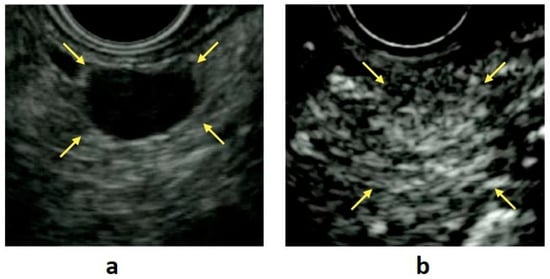

EUS enables detailed observation of the entire pancreas with high tissue resolution, without being affected by the gastrointestinal tract or subcutaneous fat (Figure 1a). In a systematic review, Puli et al. reported that EUS had a sensitivity of 87.2% and a specificity of 98.0% when used for the detection of PNENs [4]. Manta et al. reported that CT failed to detect 68.4% of PNENs < 10 mm and 15% of PNENs ≤ 20 mm in diameter [5]. Moreover, it has been reported that the sensitivity of CT is reduced for small lesions < 1 cm and that 91% of PNENs that are difficult to detect using multidetector-row CT can be detected with EUS [6]. James et al. reported in a meta-analysis that preoperative EUS consistently increased the overall PNEN detection rate by >25% after a CT scan, with or without additional investigative modalities such as MRI or ultrasound [7]. Thus, EUS is an essential modality for the detection of small PNENs.

CE-EUS is useful for the evaluation of pancreatic disease because it permits the observation of the hemodynamics of masses in real time. This technique is based on the fact that microbubbles in contrast agents are disrupted by ultrasound waves, producing signals that are detected by the ultrasound imager. Because typical PNENs have abundant blood vessels, these tumors show hypervascular contrast in the early phase, persisting until the delayed phase (Figure 1b). CE-EUS has a high sensitivity (78.9–95.1%) and a high specificity (98.7%) in the identification of PNENs [23,24].

8. Features of EUS Findings in PNENs

On EUS examination, PNENs typically appear as well-rounded, hypoechoic lesions with a homogeneous pattern and clear regular margins (Figure 1a,b). However, because PNENs grow expansively, they may cause cystic degeneration and calcification as their size increases. In these cases, PNENs often presented a heterogeneous pattern (Table 1).

Figure 1. (a) B-mode endoscopic ultrasound (EUS): a circular hypoechoic mass is seen in the body of the pancreas (yellow arrow). (b) Contrast-enhanced EUS: the mass shows early enhancement compared with the surrounding pancreatic parenchyma (yellow arrow).